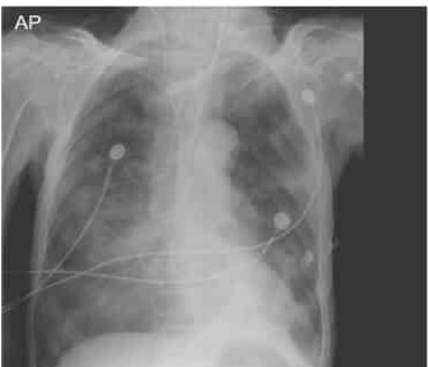

Paciente masculino, 70 anos, internado na UTI há 4 dias

com acidente vascular cerebral isquêmico, apresentou episódio

importante de aspiração alimentar. A radiografia de tórax foi

solicitada e realizada cerca de 12h após o ocorrido, sendo

observado o resultado com a imagem a seguir:

O quadro pulmonar apresentado é compatível com: